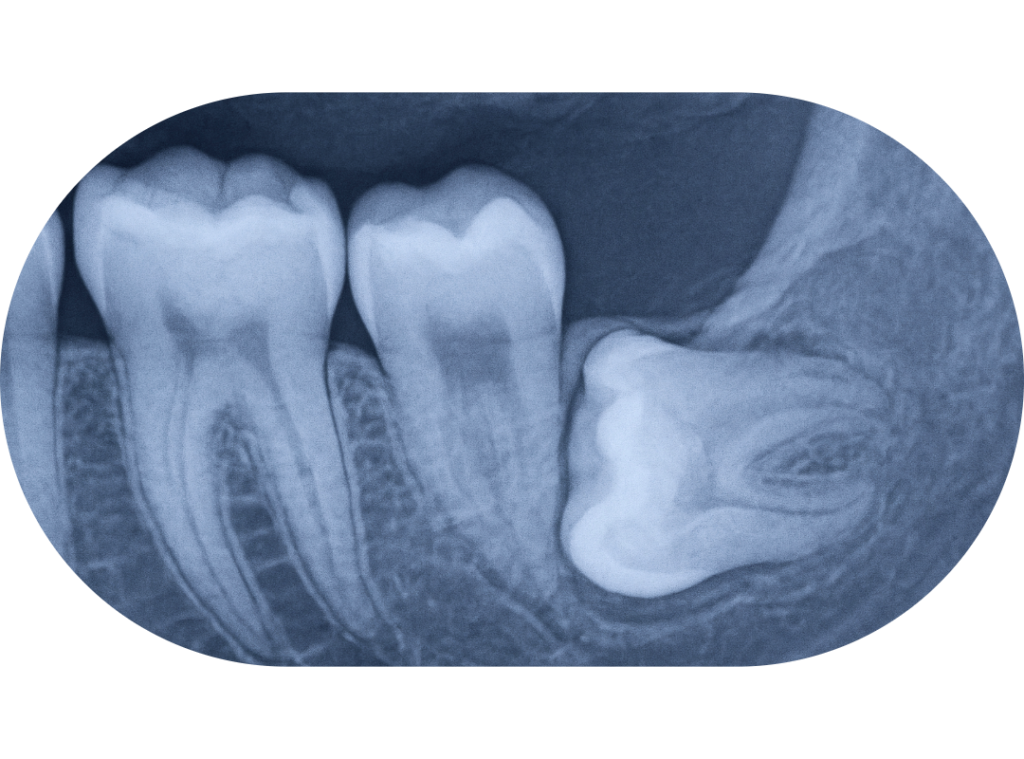

Impacted or Blocked Permanent Teeth